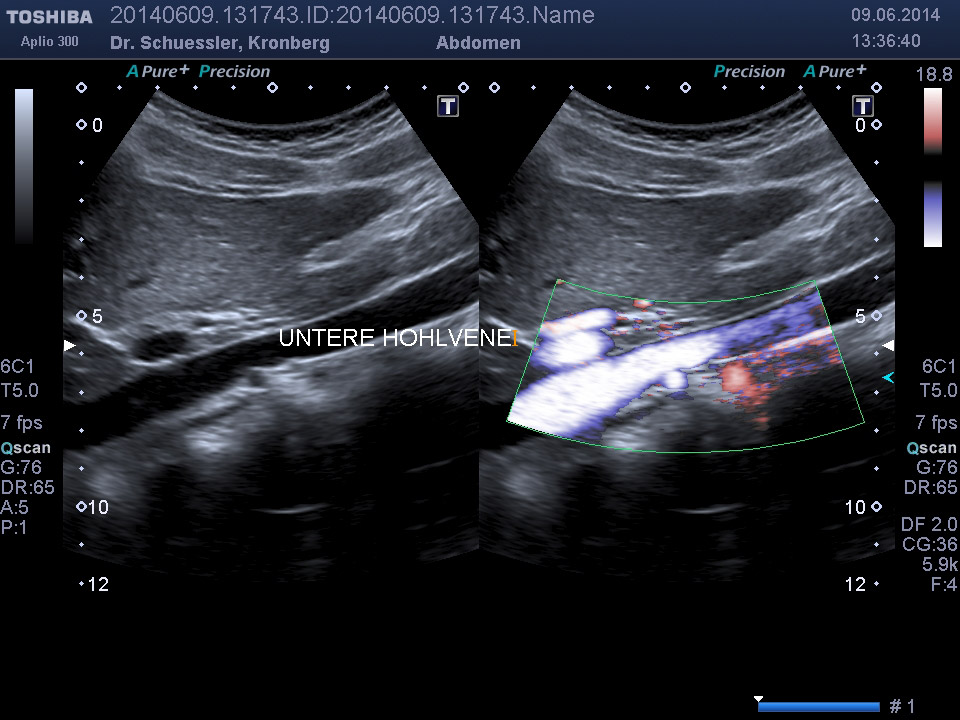

Die farbkodierte Duplexuntersuchung der Gefäße ist ein Ultraschallverfahren und gibt u.a. Auskunft über Verkalkungen, Einengungen, Verschlüsse oder Thrombosen im Bereich der Arterien und Venen.

Die Untersuchung wird angewandt zur Diagnostik von Verengungen in den hirnversorgenden Arterien, Erweiterungen (Aneurysmen) oder Verengungen der Bauchschlagader, Verengungen der Nierenarterien bei Bluthochdruck,  Venenthrombosen und zur Bestimmung des Gefäßrisikoprofils.